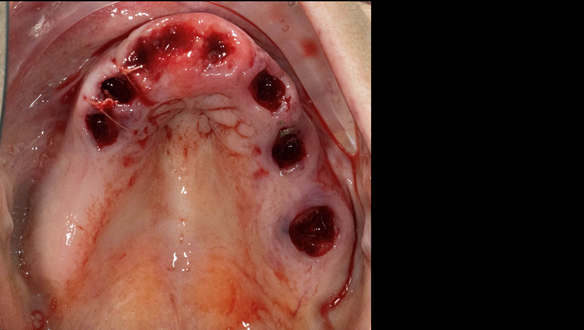

This newsletter describes in step by step detail Anne's transition from an immediate complete upper denture to a definitive complete upper denture.

The clinical situation and treatment process is shown in detail below with photographs. In addition, threre is a link to the a 45 minute webinar I gave explaing this case. I provided the clinical work and Rowan Garstang provided the technical work.